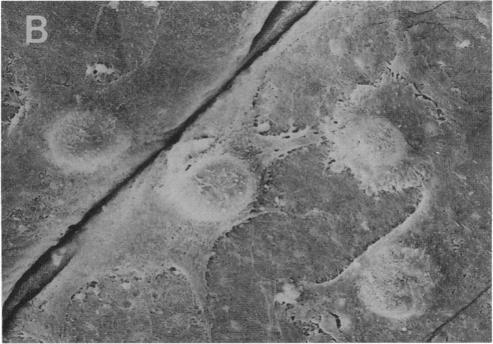

Gene therapy used in the context of delivering a therapeutic gene(s) to chondrocytes offers a new approach for treating chondrocyte-mediated cartilage degradation associated with various human arthropathies including osteoarthritis. In this study, gene delivery to human osteoarthritis chondrocytes in monolayer culture was demonstrated using two adenoviral vectors (Ad.CMVlacZ and Ad.RSVntlacZ) carrying the Escherichia coli beta-galactosidase marker gene, and a third vector (Ad.RSV hIL-1ra) containing the cDNA for human interleukin-1 receptor antagonist. At an moi of 10(3) plaque-forming units/chondrocyte, > 90% of the infected cells stained positive for E. coli beta-galactosidase activity, indicating a high efficiency of transduction. Genetically modified chondrocytes were then transplanted onto the articular surface of osteoarthritic cartilage organ cultures with and without the underlying subchondral bone. Both in situ staining of the cartilage organ cultures for E. coli beta-galactosidase activity and examination by scanning electron microscopy indicated that the transplanted chondrocytes adhered and integrated into the articular surface and continued to express transgenic protein. Chondrocytes transduced with Ad.RSV hIL-1ra and seeded onto the surface of osteoarthritic cartilage secreted high levels of biologically active IL-1 receptor antagonist. The Ad.RSV hIL-1ra-treated cartilage samples were resistant to IL1-induced proteoglycan degradation over 10 d of sustained organ culture. These data demonstrate that transplantation of transduced chondrocytes onto the articular surface protects cartilage from IL-1-induced extracellular matrix degradation.